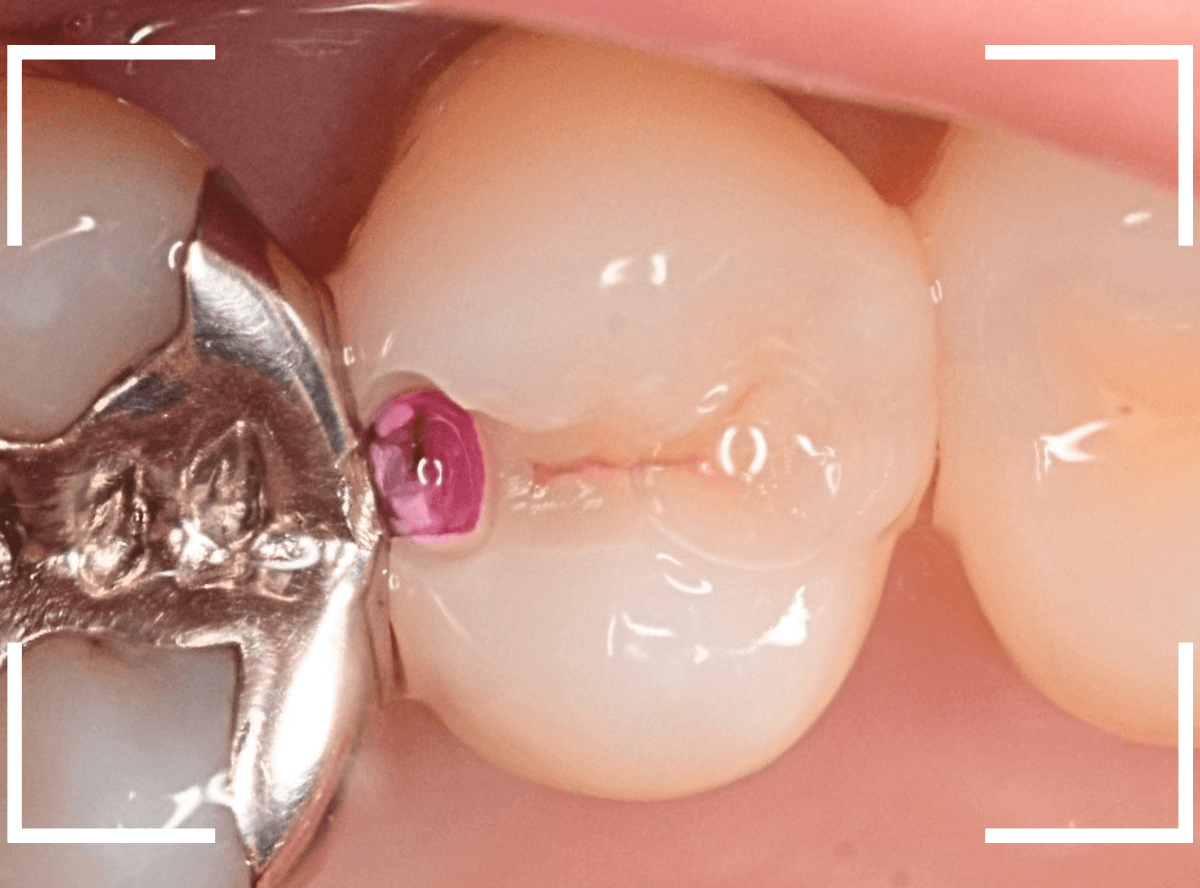

治療を開始します。

先ほどの黒く見えた部分は少し削るとすぐに虫歯が出てきました。

手前の歯まで虫歯を除去した時点で、う蝕検知液で確認します。

赤く染色されている部分が虫歯です。

思ったよりも深めの虫歯ですね。